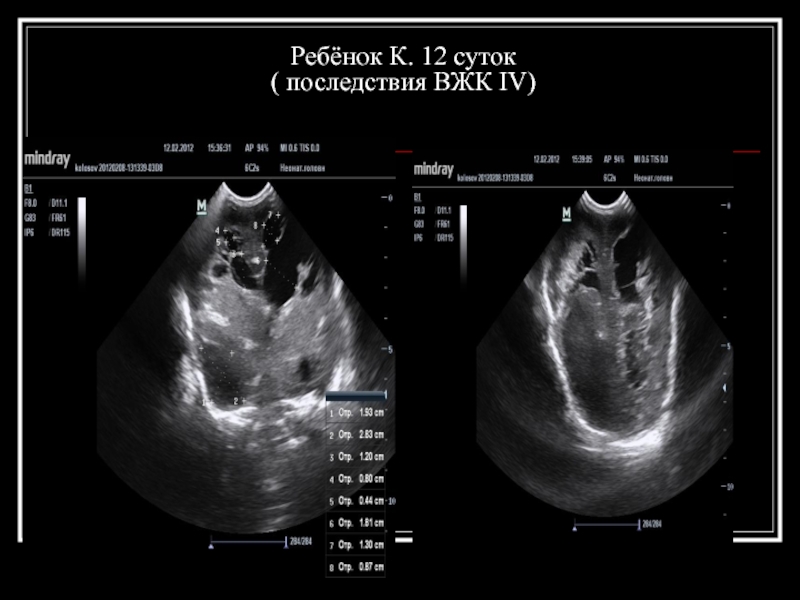

Слайд 25Ребёнок К. 12 суток ( последствия ВЖК IV)

Слайд 26Ребёнок К. 12 суток ( последствия ВЖК IV)

Слайд 27Ребёнок К. 12 суток ( последствия ВЖК IV)